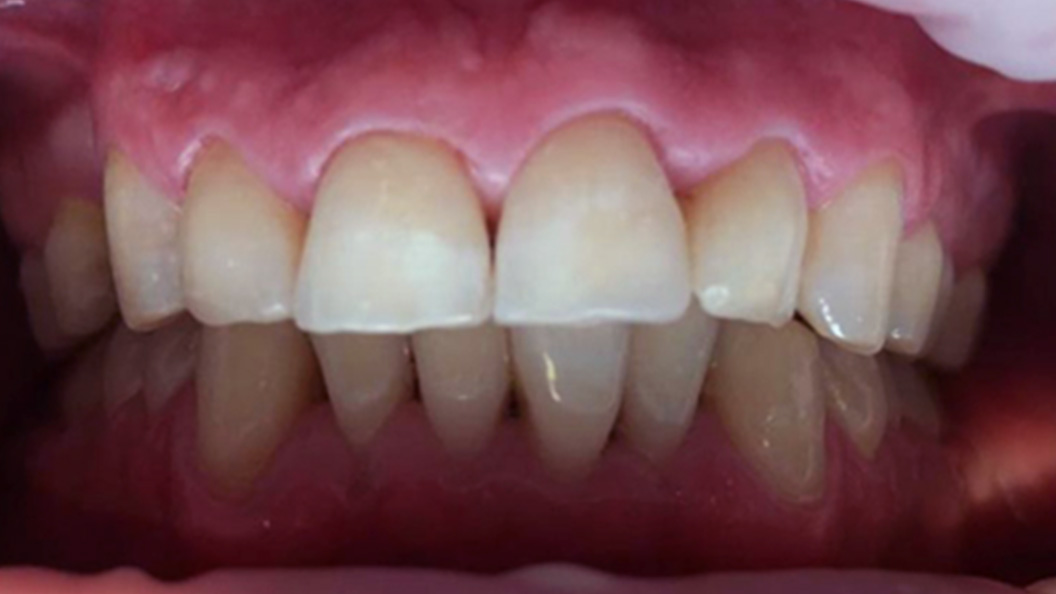

До и после лечения

В ходе процедуры Еленой Сергеевной были проведены следующие работы:

- анестезия;

- обработка и препарирование зуба;

- реставрация с использованием композитного материала.